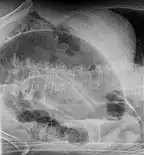

CT scan of a small bowel volvulus. It shows two juxtaposed segments of narrowing, which is the spot of mesentery rotation. The other signs indicate strangulation.- An x-ray of a person with a small bowel volvulus.